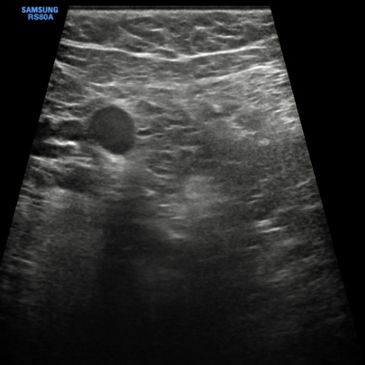

Principle: High-frequency B-mode imaging (7–15 MHz) with real-time assessment of lesion morphology, echotexture, margins, and vascularity.

Diagnostic Performance:

Role in Management:

Purpose: Focused evaluation of a region of interest identified on mammography, MRI, or physical exam.